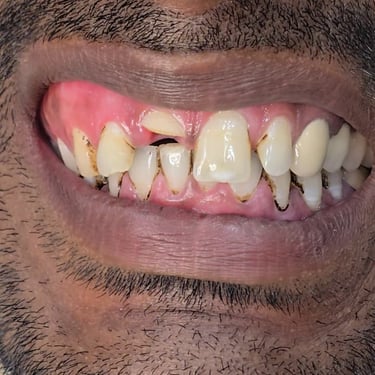

Step 1: Clinical Examination & Diagnosis

The patient’s maxillary anterior tooth (front tooth) was fractured because of trauma. On examination, the pulp was exposed and treatment planning was done for Root Canal Treatment (RCT) followed by a fiber post, core build-up, and crown placement.

Before & After Photographs

This visual journey helps patients understand the importance of timely dental treatment and how a fractured tooth can be saved.